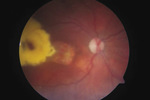

W 2008 r. pacjentka zgłosiła się do Kliniki Okulistyki Pomorskiego Uniwersytetu Medycznego w Szczecinie na badanie okulistyczne prowadzone w ramach działalności naukowej Studenckiego Koła Okulistycznego. W badaniu stwierdzono ostrość wzroku oka prawego (OP) 3/50 bokiem snp (z wywiadu na stałym poziomie od wielu lat), a oka lewego (OL) 0,9 cc -0,5 Dsph = 1,0. Ciśnienie wewnątrzgałkowe w obydwu oczach było prawidłowe. Z odchyleń od normy w przednim odcinku OP obserwowano przymglenie dolnej części rogówki z wrastającymi pojedynczymi naczyniami, będące następstwem wygojenia głębokiego owrzodzenia rogówki, które spowodowane było zaawansowanym zespołem suchego oka i niedomykalnością powiek w czasie snu. Poza tym sztuczna soczewka tylnokomorowa ufiksowana była prawidłowo, odnotowano również kapsulotomię tylną oraz fibrozę resztek przedniej i tylnej torby. W badaniu dna OP stwierdzono tarczę nerwu wzrokowego bladą, okrągłą, w poziomie dna, centralnie położony zanik siatkówkowo-naczyniówkowy o średnicy 1,5 DD oraz przylegające do niego od strony skroniowej duże skupisko wysięków twardych o średnicy 4 DD, zwężone naczynia tętnicze, siatkówkę jasnoróżową, przyłożoną (ryc. 1). W ciele szklistym zaobserwowano pojedyncze męty. Przedni odcinek oraz dno OL były prawidłowe. Pacjentka została skierowana do poradni przyklinicznej w celu dalszej obserwacji i ewentualnej diagnostyki.

W badaniu dna OP stwierdzono bladą okrągłą tarczę nerwu II położoną w poziomie dna, w plamce podejrzewano wylew podsiatkówkowy otoczony wieńcem wysięków oraz zwężone tętnice. Wgląd w dno OP był utrudniony ze względu na wysięk zapalny w ciele szklistym (ryc. 2 i 3).